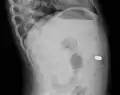

Lateral X ray showing a 9mm battery in the intestines